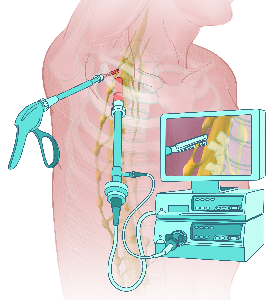

Detailreiche Fotografien aus der medizinischen Praxis ergänzen die Texte; moderne, genaue,

wissenschaftliche Zeichnungen geben Einblick in die Anatomie und die Funktion der Lunge und

anderer Organe.